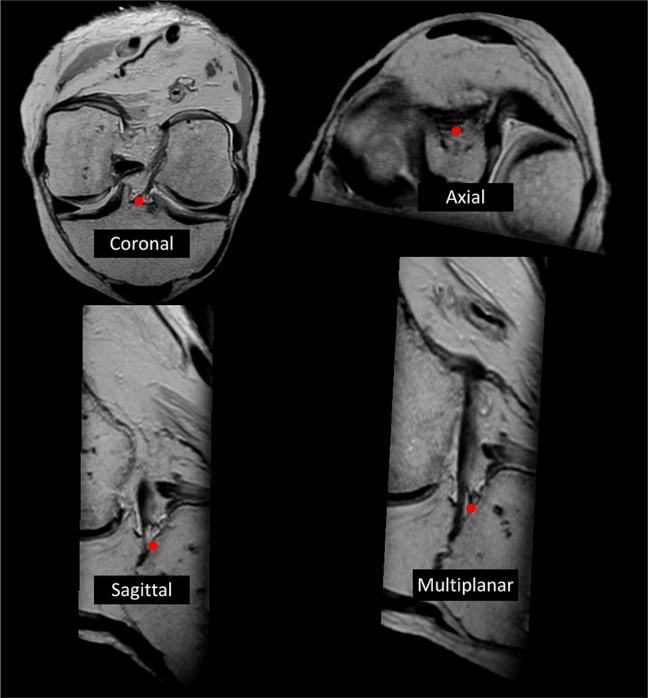

Using 3D MRI, the native ACL footprints were identified. Tunnels were created on 16 knees (8 cadavers) arthroscopically. On one knee of a matched pair, the tunnels were created based on 3D MRI measurements that were provided to the surgeon (roadmapped technique), while on the contralateral knee, the tunnels were created based on a standard anatomic ACLR technique. The technique was randomly assigned per set of knees. Postoperatively, the positions of the tunnels were measured using 3D MRI.

方法

使用3D MRI识别天然前交叉韧带足迹。通过关节镜在16个膝关节(8具尸体)上创建隧道。在配对的一个膝关节上,根据提供给外科医生的3D MRI测量结果创建隧道(路线图技术),而在对侧膝关节上,根据标准解剖前交叉韧带重建技术创建隧道。每组膝关节随机分配技术。术后,使用3D MRI测量隧道位置。